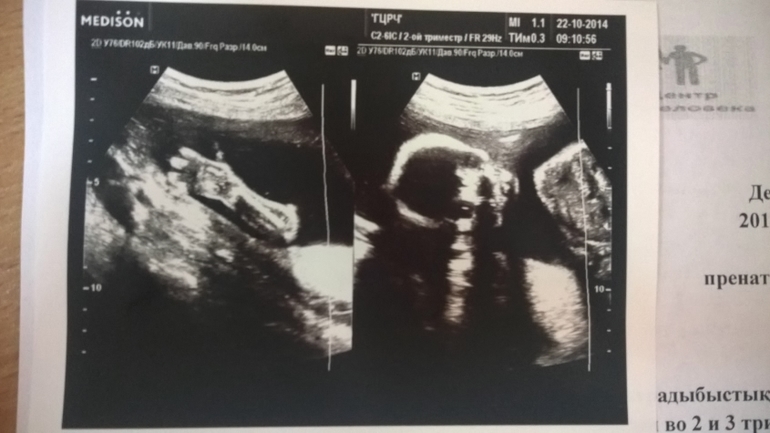

Результаты: УЗИ, КТГ, доплера, скринингаИ так, сегодня завершился еще один этап - мы прошли 2й скрининг. ттт все у нас хорошо, весиим уже 440 грамм. Ручкой маме на УЗИ махали, привет передавали))

А еще мы датчик узистки пытались оттолкнуть..не понравилось что - то. Вообще сына вялый был, спал наверное еще, да и не поварачивались личиком...кое как минут через 20 рассмотрели. ПДР так и не поменяли - 28 февраля.

Ну и наши фото)